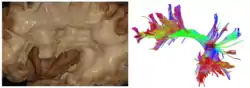

Tractography showing arcuate fasciculus | |